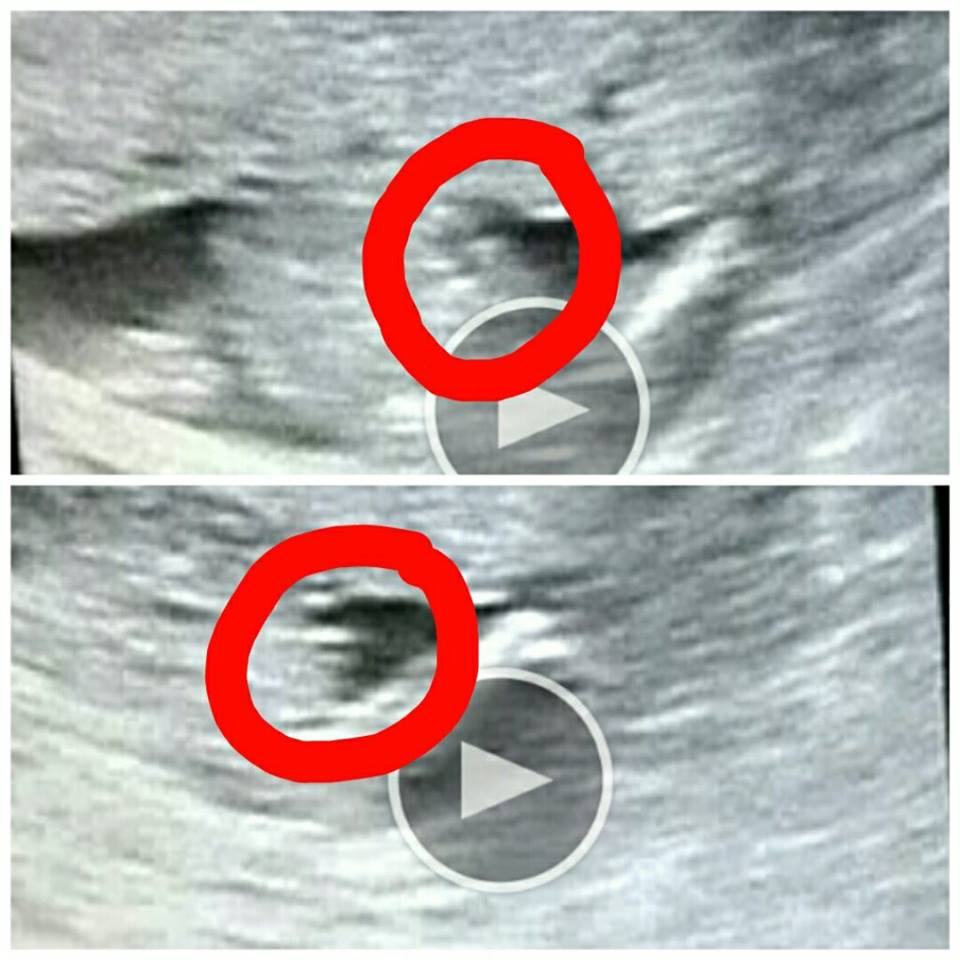

Beim heutigen (SSW 152) Ultraschall waren im Intimbereich unseres Babys 3 parallele Striche zu sehen;. SSW mittels Ultraschall feststellen, ob Sie einen Jungen oder ein Mädchen bekommen Achtung Wenn Sie jetzt noch nicht wissen möchten, ob Sie einen Jungen oder ein Mädchen bekommen, sondern sich lieber bei der Geburt überraschen lassen möchten, teilen Sie das unbedingt Ihrem Arzt mit, damit er sich nicht "verplappert". Ultraschall mädchen 21 ssw Riesenauswahl an Markenqualität Folge Deiner Leidenschaft bei eBay!.

Was sehen wir hier im US?. Ab SSW 15 kann man das Geschlecht des Babys im Ultraschall erkennen Wann wissen wir, ob es ein Mädchen oder ein Junge ist?. Ich habe in der 17SSW ein 80% Mädchenouting bekommen, leider ohne Bild, in der 21SSW wieder, mit Bild, aber die 3 Striche konnte ich nicht sehen (die sind ja typisch, bzw sollen ja die Schamlippen sein) und dann in der 30SSW hab ich ein eindeutiges Outing mit deutlichem Bild bekommen Das kannst du bei unserem USBilderThread sehen.

) zeigt eure Mädchen und Jungs US Bilder zum vergleichen ) BabyCenter Also leuteeee in der 13 16ssw wurde gesagt mädchen Da hat man 2 striche gesehen Heute war die große untersuchung bin jetzt in der 18ssw und siehe da 100%junge was. #1 Für ein Mädchen bräuchte es drei Striche Wi a kaisersemmerl sagt mein Gyn 😅 mv12 3 26 06 19, 0021 @Nasty SSW das untere Bild ist von letzter Woche, das obere war bei der NFM vor 3 Wochen Nadine_. Wie sicher geschlecht in 19 ssw (3D) hallo dr bluni, ich hatte in der 19 ssw einen 3d ultraschall der arzt meinte er sehe eine kaffeebohne ) also mädchen, er 15 SSW (Schwangerschaftswoche) Onmedad Ein besonderes Angebot ist der 3D/4D Ultraschall, mit dem Sie schon zwischen der 25 und 30.

Das sieht also schon nach Mädchen aus Dachte ich mir auch logischerweise, aber Google mal 3StricheUltraschall Merkwürdig Ich hab zwei Mädels, und da sah man zwei parallele Striche und der FA hat auch kommentiert, dass die zwei Striche das klassische USMädchenmerkmal sind. Diese Frage beschäftigt viele Paare, sobald sie erfahren, dass sie ein Baby erwarten. Hallo, für ein Mädchen sprechen 3 echoreiche parallele Streifen Vor der 14 SSW ist das kaum auszumachen NT von 1,7 mm ist im Normbereich.

SSW Hallo,Ihr Arzt hat Sie richtig informiert, wenn ich diese 3 parallelen Striche auch nicht sicher ausmachen kann Aber am bewegtem Bild sieht man das besserLiebe Grüße W Ultraschall. In der 15 SSW bewegt Ihr Baby nun regelmäßig seine Arme, Beine und den Rest der Körpermuskulatur Der kleine Fetus kann sogar an seinem Daumen saugen Lesen Sie mehr über Sie und die Entwicklung Ihres Babys nach 15 Wochen. Laut Paragraph 15 des Gendiagnostikgesetzes (GenDG) darf ein Arzt das Geschlecht erst nach Ablauf der 12 Schwangerschaftswoche mitteilen Dabei spielt es keine Rolle, ob das Geschlecht im Ultraschall oder im Zuge der Pränataldiagnostik erkannt wird Hintergrund dieses Gesetzes ist, dass bis zur 12.

Wenn dein Baby beim Ultraschall mitspielt, kannst du jetzt herausfinden, ob es ein Mädchen oder Junge wird Dennoch gilt Es haben sich schon viele Ärzte geirrt und nach der 16 SSW oder gar nach der Geburt festgestellt, dass das Mädchen, ein Junge ist – oder anders herum. Hallo, für ein Mädchen sprechen 3 echoreiche parallele Streifen Vor der 14 SSW ist das kaum auszumachen NT von 1,7 mm ist im Normbereich. Na die drei striche sollen die schamlippen darstellen Ich habe bisher immer nur eine vermutung zu einem mädchen outing bekommen ich hoffe bei meinem nächsten Fa Termin in 3 Wochen, bekomm ich auch so ein bild mit drei strichen grüße fee und baby ssw.